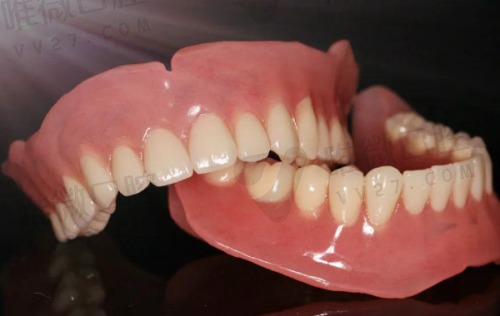

- 活动义齿(隐形义齿、支架义齿)